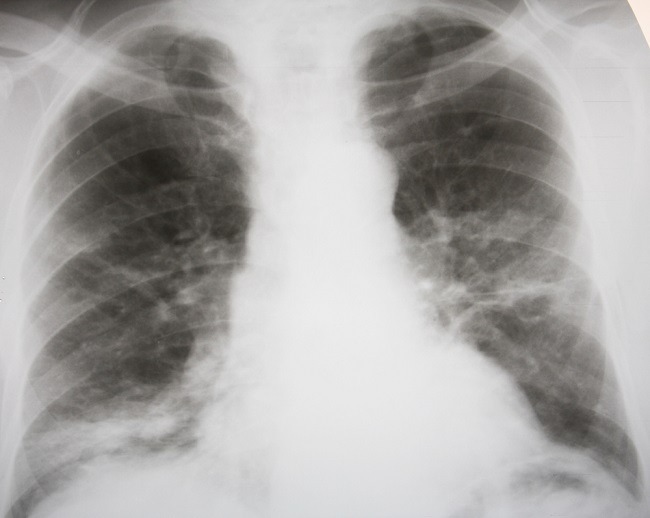

Bronkitis Kronis Interpretasi Radiologis X Ray Doktermuslim